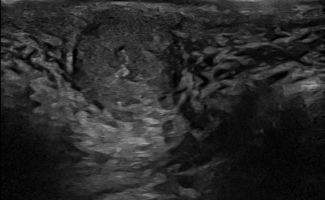

Πολλές αλλοιώσεις και παθήσεις μπορούν να απεικονιστούν υπερηχογραφικά και να μελετηθούν αξιόπιστα με τη βοήθεια του Έγχρωμου Doppler και της Ελαστογραφίας .

- Όγκοι των σιελογόνων αδένων ή της γλώσσας